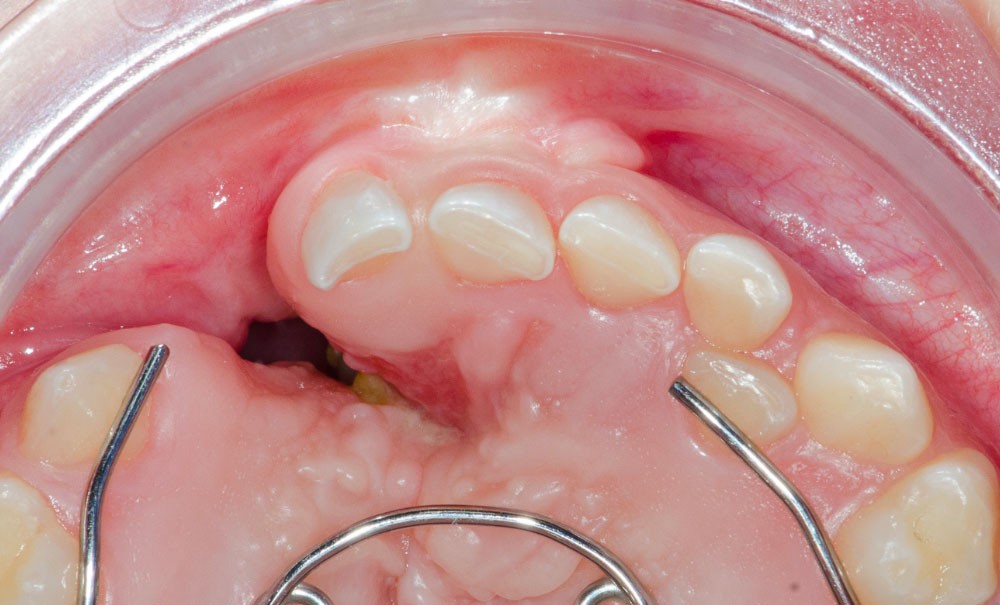

La fente alvéolaire divise le maxillaire en deux ou trois fragments, ce qui perturbe sa croissance et empêche l’éruption de la dent définitive. Quand et comment restaurer la continuité du maxillaire ?

Les fentes labiales et palatines sont les malformations congénitales de la face les plus fréquentes, avec une incidence moyenne de 1/700 naissance dans le monde. Elles ont des répercussions esthétiques et fonctionnelles importantes, la cavité orale étant au carrefour de nombreuses fonctions. La phonation est perturbée par la mauvaise occlusion entre le voile du palais et la paroi postérieure du pharynx, provoquant fuite d’air et voix nasonnée. L’oreille moyenne peut être atteinte par une mauvaise aération de la trompe d’eustache qui s’ouvre habituellement par la contraction des muscles tenseurs et releveurs du voile du palais, ce qui provoque des otites à répétition et parfois une perte d’audition. L’alimentation est bien entendu difficile tant que la fente labiale, et surtout palatine, n’est pas refermée.

La prise en charge des patients concernés est par nature pluridisciplinaire et s’effectue par des équipes spécialisées regroupées en centre de compétences. En moyenne, ces enfants vont bénéficier de six interventions chirurgicales jusqu’à l’âge adulte notamment pour restaurer la continuité de la lèvre, du palais, et de l’arcade maxillaire.